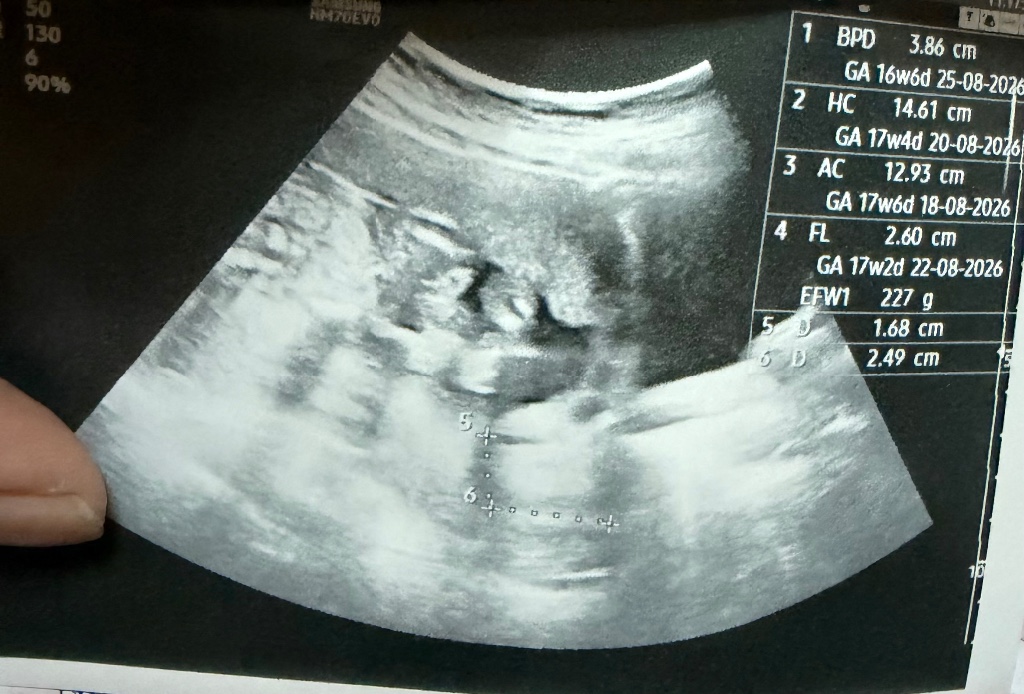

วิเคราะห์รูปอัลตร้าซาวด์

ช่วยดูภาพอัลตร้าซาวด์หน่อยค่ะไปซาวด์โรงบาลมาดูไม่ออกเลยค่ะ